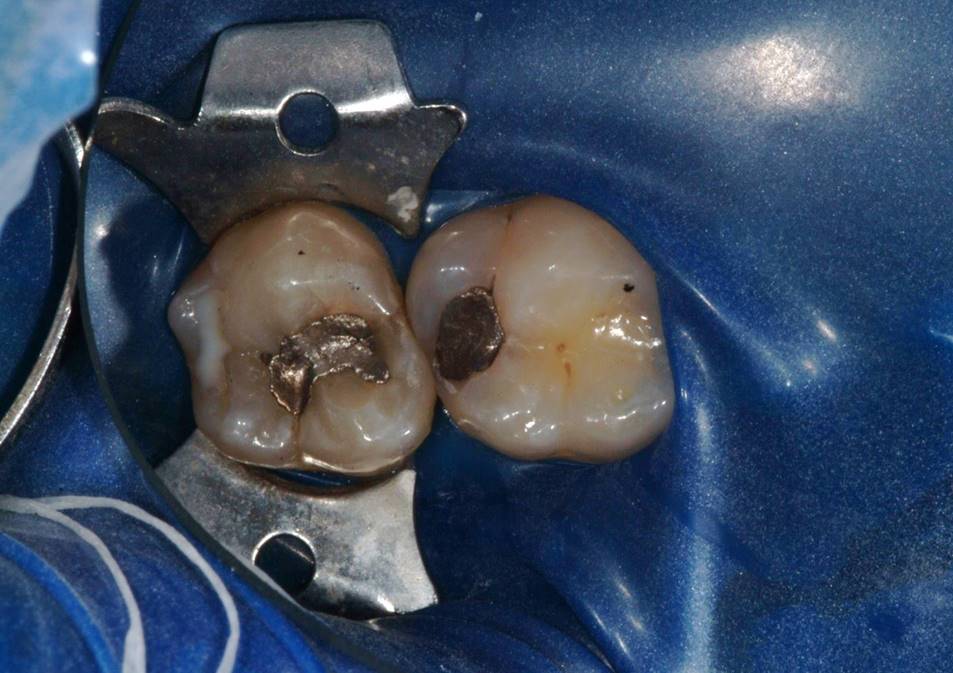

Fig 6. The amalgam restorations were thoroughly removed and the cavities prepared, after which caries indicator was applied to ensure the presence of only healthy, caries-free tooth structure.

Figure 6